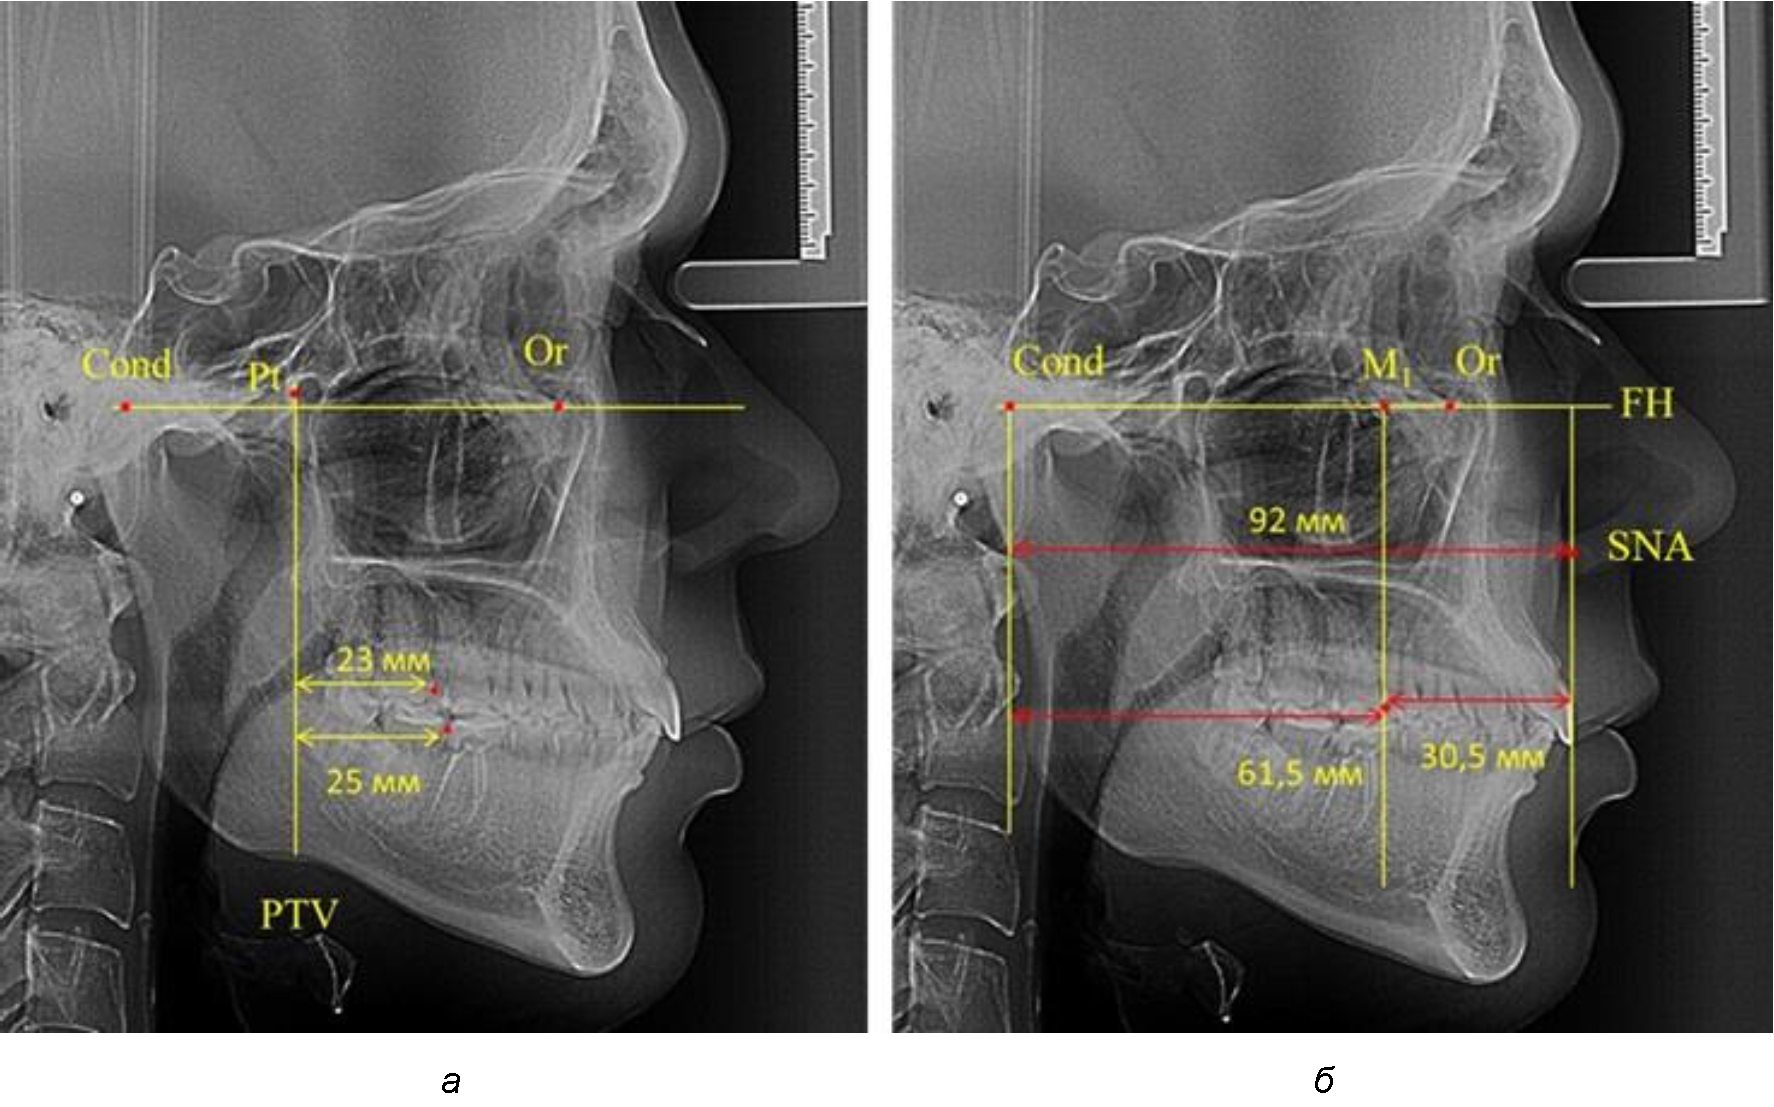

В то же время при увеличенном расстоянии от крыловидной вертикальной плоскости PTV до дистальной поверхности верхнего первого постоянного моляра, равное 23 мм, сагиттальный размер гнатического отдела составил 92 мм. При этом отношение кондилярно-спинального расстояния к кондилярно-молярному размеру (30,5), так же, как и при малых размерах, было близким к коэффициенту 1,5, что представлено на рис. 3.

Рис. 3. Особенности положения первых моляров по R. E. McDonald (а) и по предложенному методу (б) при увеличенном молярно-крыловидном расстоянии

Таким образом, наблюдалась эффективность использования относительных показателей при определении положения первых постоянных моляров. При этом наиболее целесообразно и с методологической точки зрения верным, было использование медиальной поверхности первого постоянного моляра. Построенная таким образом молярная линия отграничивала отдел зубной дуги с замещающими зубами от дистального отдела с добавочными зубами постоянного прикуса, в частности, постоянных моляров.